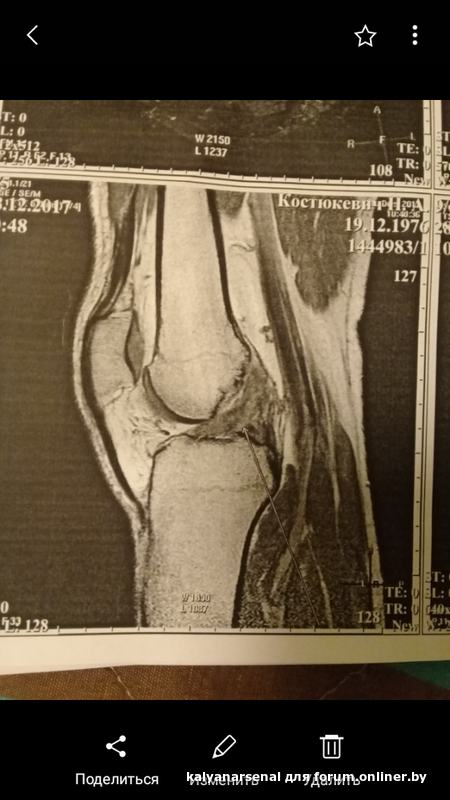

Всем привет! Вкратце моя история(возможно кому-то пригодится). Травма колена в октябре 2017. Через 2месяца (в декабре 2017) делаю мрт1(на Семашко).В заключении: вероятен полный разрыв пкс(сравнив мои снимки с аналогичными при полном разрыве в интернете,даже я согласился.Связки нет и не прослеживается),повреждение заднего рога внутреннего мениска.Нервничаю,сплю плохо,все время вспоминаю как получил травму(типа,зачем я тогда прыгнул,зачем я вообще после 10летнего перерыва пошел играть в футбол с бывшими футболистами,ах если бы не так,а вот так и т.д.)Штудирую литературу,форумы,блоги по данной теме.Нога беспокоит все это время:ходить могу только ровно ставя стопу,любые резкие и скручивающие движения доставляют дискомфорт.В покое боли нет. При ходьбе и беге ноет. За эти 5месяцев после травмы был на консультациях у врачей травматологов-ортопедов:в 6ой больнице(3раза),в НИИ травматологии на Кижеватова(3раза),в военном госпитале(2раза). Воробьев Сергей Николаевич из госпиталя,конечно,выделяется на фоне остальных врачей.По своим человеческим качествам,профессионализму и индивидуальному подходу к пациенту.С ним хоть нормально поговорить можно по своей травме.Попадались мне просто пару раз,скажем так,"небожители в халатах",для которых ты-"челядь".Причем,я за это еще и платил!Мне как-то это до фонаря,просто рассказываю о своих ощущениях во время визитов.Ну что,мысленно готовлю себя к операции по пластике,размышляю как бы все устроить:работа,семья,деньги и т.д.Единственное,все время сомневаюсь в правильности заключения мрт.Потому что ни один из врачей не подтвердил тестами нестабильность моего колена+не было у меня отека(важный фактор при разрыве пкс).20 дней физиопроцедур(лазер и магнит)эффекта не возымели,сам пытаюсь делать дома лфк,пью хондропротекторы,5дней какие то таблы пропил противовоспалительные(уже не помню какие,травматолог один выписал) и сделал в колено укол кеналога. Короче,без толку. Решаюсь сделать еще одно мрт2 на Кижеватова в НИИ. Заключение мрт2:застарелое повреждение пкс после частичного разрыва.Анатомическая целостность полностью не нарушена!Девушка-расшифровщица показывает мне фото и даже я-дилетант вижу свою связку! Она говорит,что даже и разрыв небольшой был,не более 50процентов а то и меньше!Никакой пластики тебе,парень,не надо!Про мениск, ну да, говорит,повреждение небольшое есть, но оперировать не стОит.Я на крыльях лечу в НИИ на консультацию и все подтверждается:пластика не нужна,мениск незначительно поврежден,но обойдется без артроскопии,лечение консервативное! Восстанавливать объем движений,эластичность связочного аппарата,не помешают опять физиопроцедуры,лфк и массаж.И знаете,после этого второго мрт и вправду стала появляться какая-то динамика,и меньше ныть стало колено при незначит нагрузках.Чувствую с каждым днем себя все лучше и лучше.Хожу в тренажерный зал.Ем желатин(вычитал где-то) и делаю желатиновые компрессы на ночь,хоть жена-врач и смеется с меня(ты б еще уринотерапией,говорит,занялся).Стал больше пить воды.(Для суставов надо.Для выработки синовиальной жидкости)Сейчас сойдет вся эта "чача"-буду делать пробежки.Вот такая история.Это к тому,что всякое бывает и с выводами торопиться не стоит.Если у врача или у вас есть какие-то сомнения по диагнозу,травме,симптомам и т.д.,подождите немного,посмотрите как будет развиваться ситуация дальше,в конце концов через какой-то промежуток сделайте повторное мрт в другом центре.Всем побольше здоровья,что б без травм! Ну а если уж так сложилось-терпения,везения и опять-таки здоровья!

P.P.S. Вверху под спойлерами 2 фото-после мрт1 и после мрт2. Крестообразная связка на первом фото как бы отсутствует(стрелочка на это указывает),а на втором черного цвета внутри сустава.

Всем привет! В декабре 2017 сел завязывать шнурки, неудачно встал и хрустнуло колено. МРТ показало то, что можно увидеть на фото.

Разрыв заднего рога латерального мениска. Болит при сгибании. Сам хожу в тренажерный зал и хочу продолжить ходить.